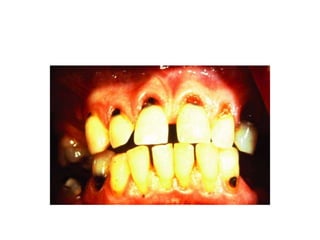

STATION 2 • A70 YEAR MALE PATIENT COMPLAINS OF PAINFUL AND LOOSE TEETH ,BLEEDING WHILE BRUSHING AND PASSING FINGER OVER IT AND HE IS NOTED WITH BAD BREATH WHILE SPEAKING . • ON EXAMINATION YOU NOTICE THIS ……..

ANSWER THE FOLLOWING 1.WHAT IS THE LIKELY DIAGNOSIS ? 2. WHAT ARE THE PREDISPOSING FACTORS OF THIS CONDITION? 3. WHAT ARE THE PREVENTIVE MEASURES OF THIS CONDITION? 4. HOW WILL YOU TREAT THIS CONDITION ?